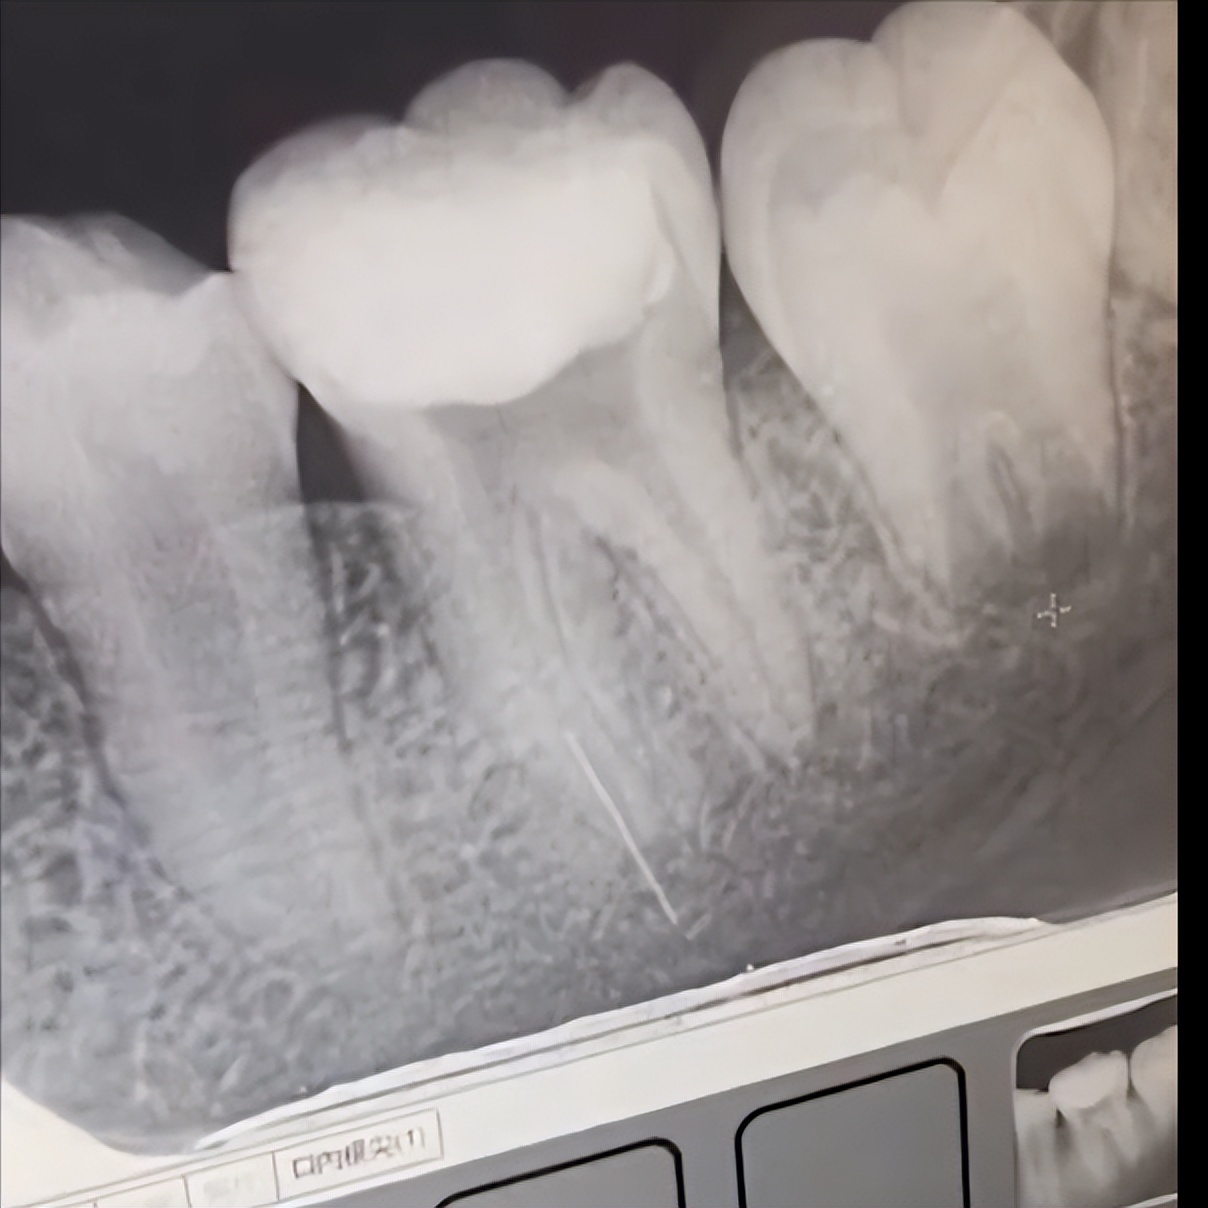

上个月,她带着年仅13岁的女儿去医院做根管治疗,第一次去还好好的,结果第二次去的时候却被医生告知: 做根管治疗的针管断在牙齿里了。

唐妈妈看到医院提供的X光片时,只觉得脑瓜子嗡嗡的,因为 断掉的根管特别长,而且离神经特别近,这要是有个万一......

但这种情况,一般是需要断针位于牙体下三分之一,但未超出根尖孔才行,上文案例中,从X光片可看出, 断针已经刺穿了牙体,超出了根尖孔 ,这种情况直接封管填充,多多少少有些碰运气的成分在里面,因为 一旦引起炎症,这颗牙大概率难以保留。

像前文13岁小女孩这种情况,其实目前来说确实是最佳的处理方式,因为断针太长,而且位置极深,取出难度极大,甚至可能需要拔除牙齿。老黑相信,老教授决定封管,一定是因为目前女孩并未出现炎症反应, 且断针和牙神经并没有处在同一水平面 ,不会对神经造成影响,只要后续没有并发炎症,也不会对小女孩的健康造成任何影响。